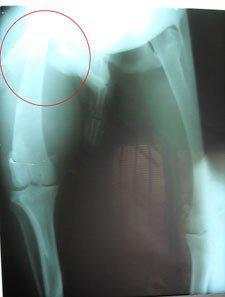

Kor es un galgo joven, rescatado de un vida dura, buscando comida y resguardándose del frío o la lluvia. Tiene la una fratura en la pata trasera que necesita operación. Es un perro muy noble y tranquilo, muy agradecido de que le prestes un poco de atención.